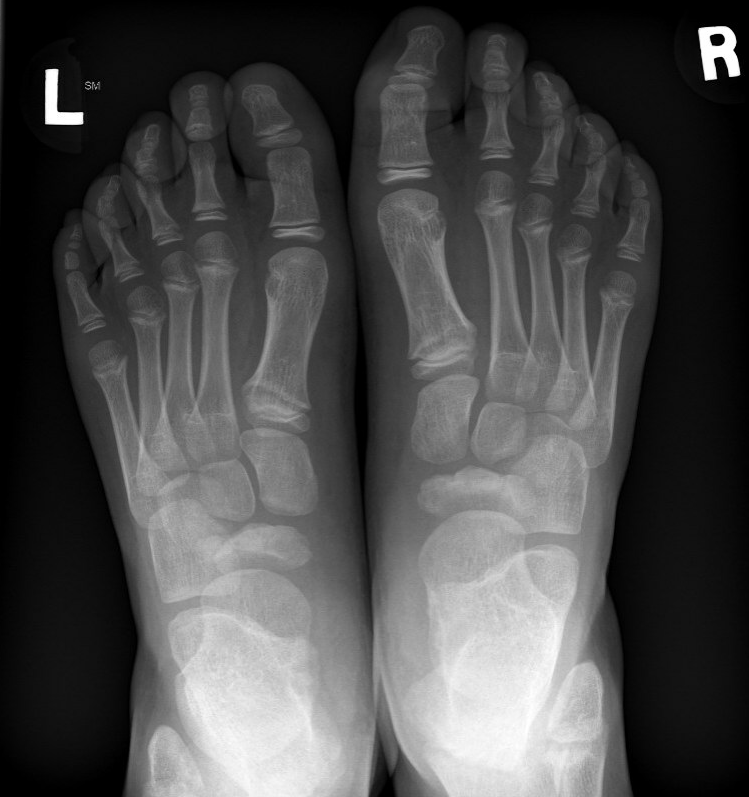

X-ray

Flattening / sclerosis / fragmentation of navicular